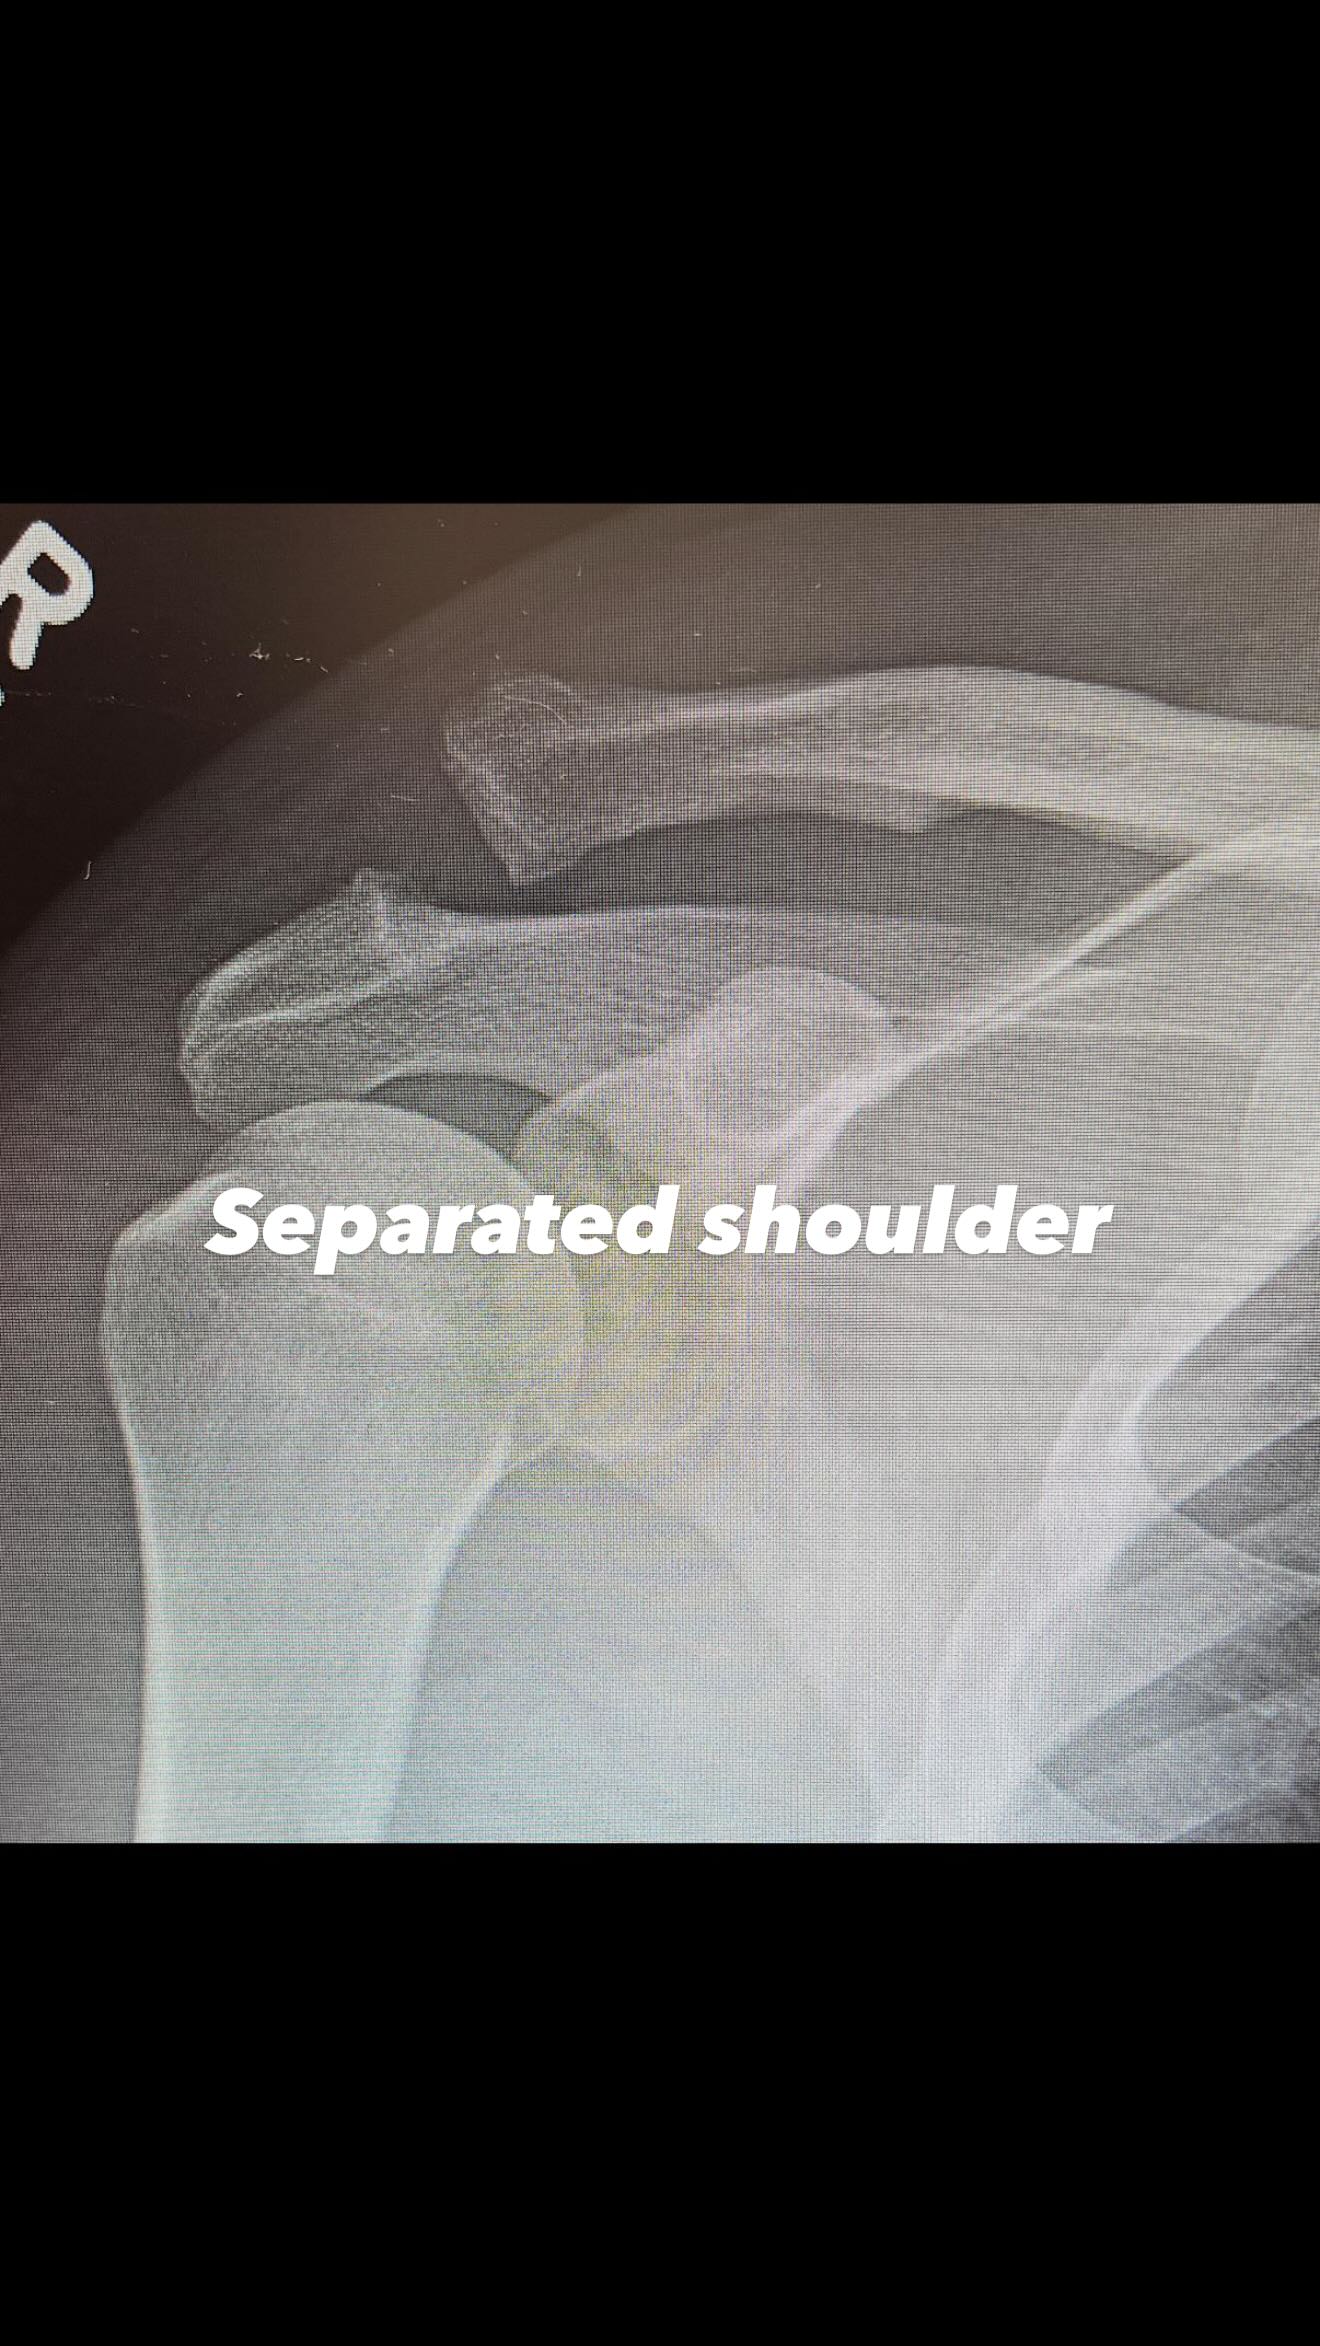

Ο ηθοποιός δημοσίευσε δύο φωτογραφίες μέσα από το νοσοκομείο, στις οποίες φαίνεται ο σπασμένος του ώμος στην πρώτη και η βίδα που τοποθέτησαν οι γιατροί στη δεύτερη.